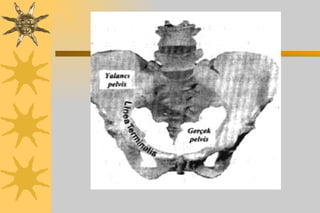

Yol=Pelvis Android Jinekoid Andropoid Platipelloid

Gynekoid tipte pelvis - android tipte pelvis

Andropoid tipte pelvis –Platipelloid tipte pelvis

Jinekoid Tipte Pelvis Kadınlarda en sık görülen ( ortalama % 50 )pelvis tipidir.

Andropoid Pelvis Tipi Beyaz ırktan olmayan kadınlarda daha sıktır.  Beyaz ırktan kadınların % 25’ inde görülür.  Baş sıklıkla oksiput posteriyor pozisyondadır ve bu şekilde doğar.

Android Tipte Pelvis Doğum için en kötü prognoza sahiptir.  Subpubik açı dardır İç rotasyon spontan olarak yapılamaz Kadınların 1/3’ünde görülür

Platipelloid Pelvis Tipi En nadir görülen pelvis tipidir( < %3) Başın pelvise girmesinde güçlük vardır.